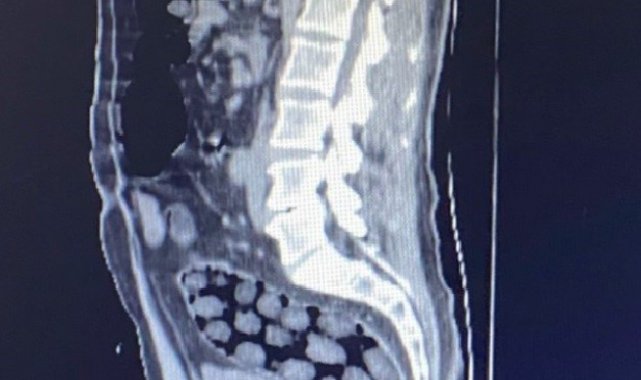

Bitlis Valiliğinden yapılan açıklamada, uyuşturucu ile mücadele kapsamında elde edilen istihbari bilgiler doğrultusunda Tatvan'da durdurulan bir otobüste yabancı uyruklu 3 yolcunun yakalandığı belirtildi. Açıklamada, "Bitlis Emniyet Müdürlüğü Narkotik Suçlarla Mücadele Şube Müdürlüğü ve İstihbarat Şube Müdürlüğü ekiplerince gözaltına alınan ve Tatvan Devlet Hastanesine sevk edilen şüphelilerin röntgen ve tomografi görüntülerinde mide ile bağırsaklarında çok sayıda yabancı cisim bulunduğu tespit edilmiş, yapılan tıbbi müdahale ile şüphelilerin paketleyerek yuttuğu toplam 91 adet daralı ağırlığı 1 kilo 126 gram metamfetamin maddesine el konulmuştur. Şüpheliler, çıkarıldığı adli mercilerce tutuklanarak cezaevine gönderilmiştir. Hemşehrilerimizin huzuru ve güvenliği için uyuşturucu madde imalatı, kaçakçılığı ve kullanımına karşı yürütülen kararlı mücadelemiz devam edecektir" denildi.